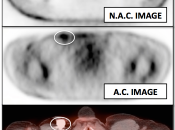

Value of Non-Attenuation Corrected (NAC) Images

Resolving Attenuation Correction Artifacts:

The CT images obtained during an exam are not only used for “anatomic” interpretation. They are also used for “attenuation correction” (AC) of the PET images, generating the much more useful AC PET images used for interpretation.

Unfortunately, attenuation correction of PET images can result in falsely elevated metabolic activity in regions of high CT density (e.g. metallic devices, oral contrast, calcification).

In such cases, these areas must be reviewed on the NAC (non-attenuation correction) images. If these regions are not also hypermetabolic on the NAC images, then their apparent increased FDG-uptake on the AC images is artefactual.

This phenomenon is almost exclusively seen with older PET/CT scanners, as most modern scanners utilize newer algorithms that do not “over-correct” in these areas of increased density.